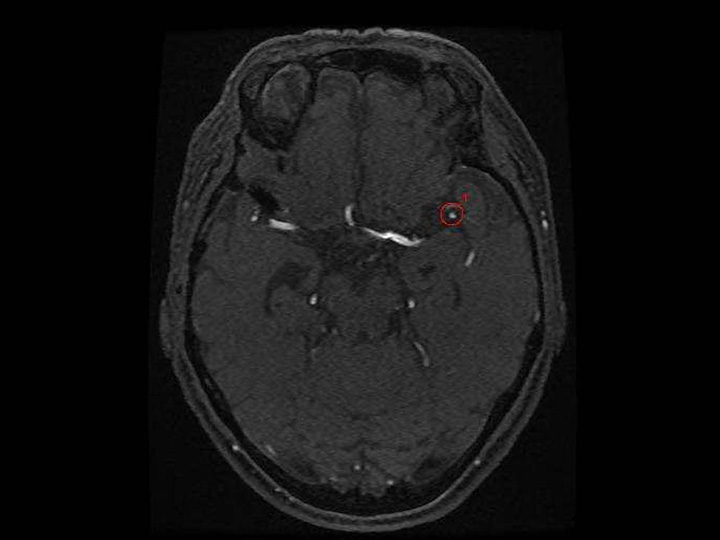

頭部MR×動脈瘤

EIRL aneurysm

頭部MRA画像より、動脈の瘤状の変形に類似した候補点を検出します

- 脳ドックの読影補助として

エルピクセル株式会社より提供を受けている医療機器「医用画像解析ソフトウェア EIRL aneurysm」を搭載しております。